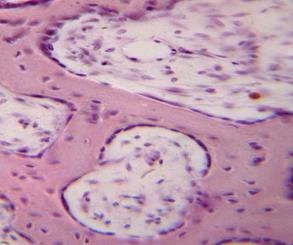

Структура грубоволокнистой костной ткани: наглядные примеры